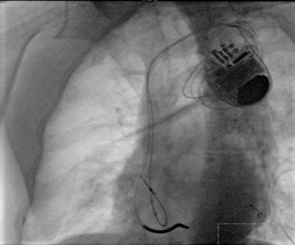

? CRT-D成功植入

?“它的技術(shù)難點在于左室電極的植入”。朱彬介紹,除了常規(guī)的由于心臟擴大變形所致的冠狀靜脈竇口位置改變,自身冠狀靜脈解剖異常等問題外,傳統(tǒng)的左室電極安置后存在起搏位點選擇性小,起搏時容易出現(xiàn)膈神經(jīng)或膈肌刺激、起搏高閾值、為保證穩(wěn)定性將電極植入心尖而出現(xiàn)心尖部起搏,為避免心尖部起搏避開心尖位置但卻出現(xiàn)電極不穩(wěn)定術(shù)后移位等諸多問題。而左室四極電極導(dǎo)線由于可以有多個起搏位點和多種起搏向量的選擇,可一次性解決上述難題,能做到“電極植入心尖,起搏心底”。綜合患者具體情況,為提高手術(shù)成功率,降低手術(shù)風(fēng)險,朱彬決定在該手術(shù)中使用目前國內(nèi)最新型的左室四極電極。

因患者病情重,基礎(chǔ)疾病多,朱彬評估患者術(shù)中可能會出現(xiàn)三大嚴(yán)重并發(fā)癥:術(shù)中發(fā)生急性左心衰、術(shù)中再發(fā)惡性心律失常、心肌穿孔。為保證手術(shù)成功開展,在華西醫(yī)院教授的指導(dǎo)下,醫(yī)院成立了三個小組來保障此次手術(shù):第一組由主刀醫(yī)生帶領(lǐng)的手術(shù)團隊組成,負(fù)責(zé)臺上手術(shù)實施;第二組由心血管內(nèi)科病房醫(yī)護人員組成,在臺下積極防治心衰及惡性心律失常;第三組由醫(yī)院心胸外科及麻醉科醫(yī)生組成,以備在出現(xiàn)心肌穿孔保守治療無效情況下緊急開胸修補。所幸術(shù)中第一小組和第二小組通力配合,手術(shù)順利,患者無明顯不適,手術(shù)耗時兩個多小時成功完成。術(shù)后患者康復(fù)出院。